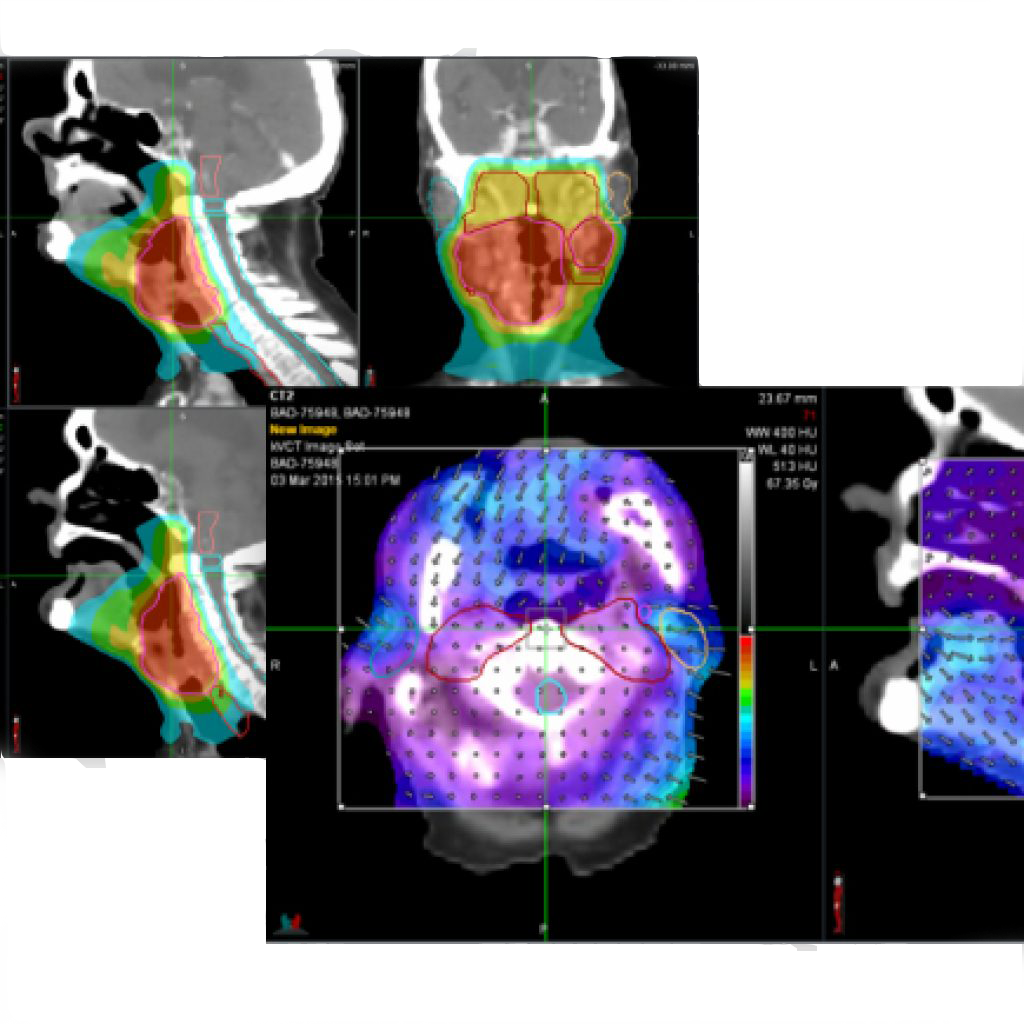

Confident Adaptation with Integrated kVCT Helical Imaging

Clinicians need high-fidelity imaging to guide plan adaptation. ClearRT® brings fully integrated, high-fidelity kVCT imaging to the Radixact® System. ClearRT provides unprecedented soft-tissue visualization that empowers clinicians to see more, know and do more — giving confidence in plan adaptation.

• Flexible field of views allow for right-sized anatomical imaging and an appropriate spatial resolution

• Increase patient throughput with faster patient imaging and registration times

• Confidently evaluate plan adaptation and use images for re-planning, when appropriate, with high-fidelity, HU-accurate image quality for contrast resolution